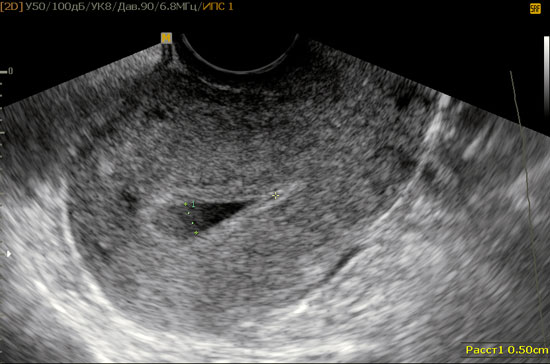

узі матки при ендометриті

За допомогою УЗД матки можна діагностувати збільшення матки в розмірах, запізнювання її інволюції після пологів, наявність в порожнині матки рідини або залишків плаценти, крові, наявність тромбів у венах оточуючих матку, поширення запалення на маткові труби і формування гидросальпинкса і піосальпінксу.

Часто протягом ендометриту, навіть гострого не має яскраво вираженої симптоматики і може маскуватися під загальне нездужання, застуду, втому. Якщо у жінки присутні фактори ризику, про які згадувалося раніше, їй слід відвідати лікаря для уважною діагностики. При стертою симптоматикою велику допомогу надає застосування узі матки, яке в нашій клініці проводиться профільним фахівцем - акушером -гінеколога. Це дозволяє заощадити цінний час, коли необхідно починати лікування ендометриту. Якщо прийом акушера -гінеколога проводиться без застосування узі, то є велика ймовірність пропустити уповільнені або безсимптомні варіанти перебігу ендометриту. При своєчасному початку лікування і грамотному застосуванні антибіотиків ендометрит проходить для жінки без наслідків.